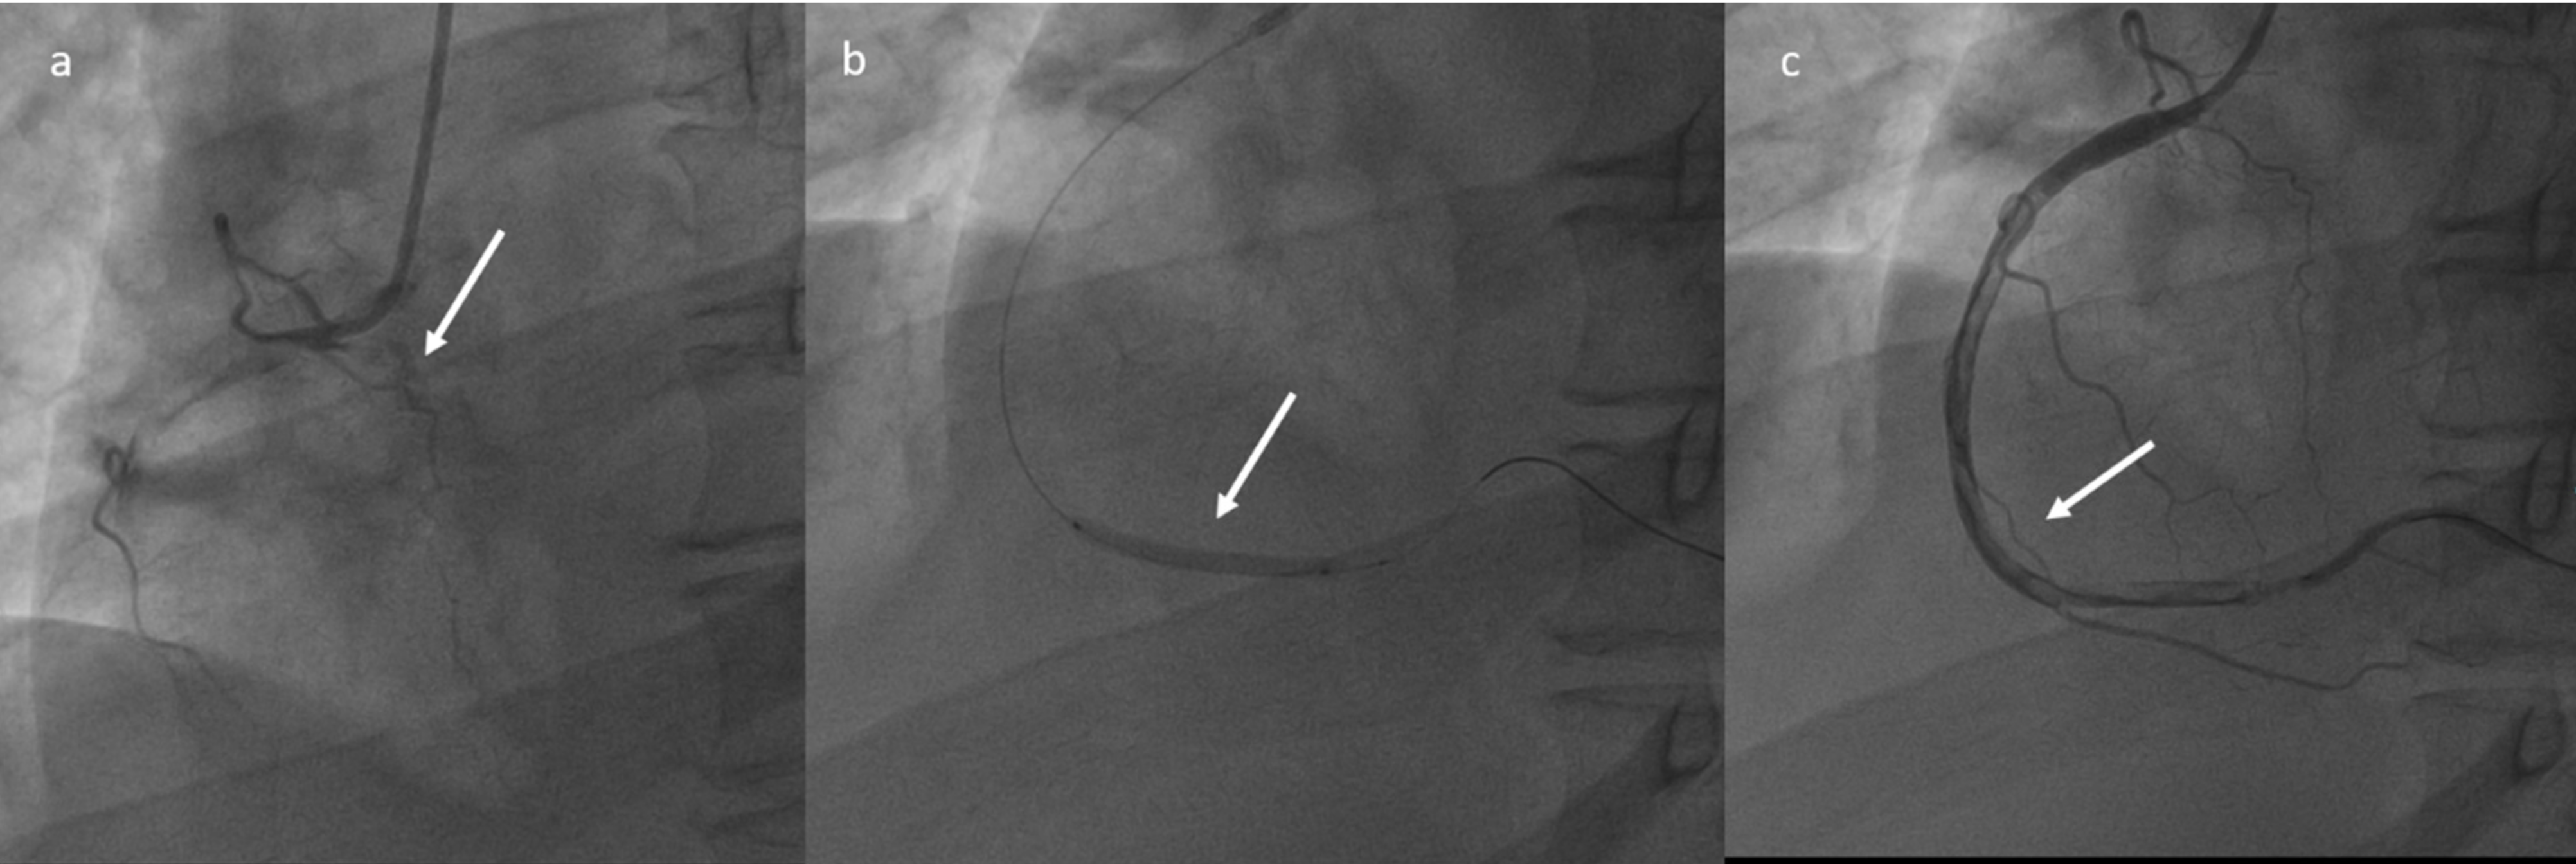

2. Case